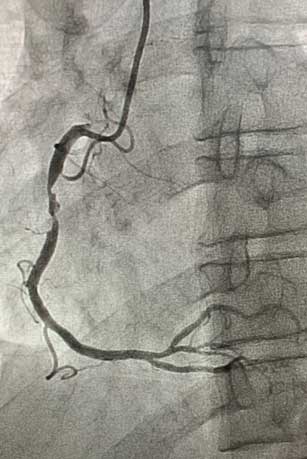

患者为45岁男性,因间断发作剑突下疼痛10天就诊于我院心血管内科门诊,完善检查后以“冠心病、不稳定型心绞痛”收入心血管内科病房。冠脉造影示:右冠近中段90%节段性狭窄,与冠脉CTA诊断一致。患者右冠状动脉近中段存在重度狭窄病变,有植入冠脉支架指征。心血管内科介入团队在赵慧强主任的带领下,针对此患者制定了个体化介入治疗方案:患者的病变特点为右冠状动脉近中段病变,无严重钙化、迂曲,非左主干病变、分叉病变、小血管病变,且患者年龄较轻,综合考虑远期预后效果,此患者适用于植入生物可吸收支架。冠脉介入团队进行了详细的术前讨论和充分的准备,经过患者同意后,为其行生物可吸收支架植入术。术中,经过充分预扩张处理右冠状动脉近中段狭窄病变后,成功于右冠状动脉病变处植入一枚生物可吸收支架。术后即刻复查冠脉造影:右冠状动脉中段支架膨胀贴壁良好,手术成功。

生物可吸收支架植入术后.jpg术后